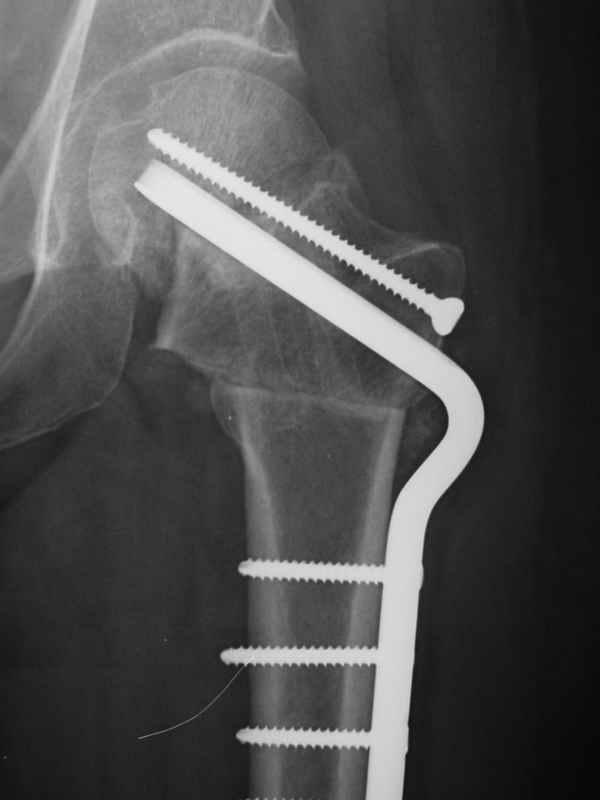

Stephen Kottmeier 17 Октябрь 2005, 21:05

friend

dhs will not correct improper biomechanical environment and may further compromise vascular

integrity consider establish vascular status via mri

and if viable follow with proximal valgus osteotomy

case provided s/p failed fixation

Отправитель: Peter Trafton 17 Октябрь 2005, 21:21

I think that this 31 yo deserves a try with valgus osteotomy, as so nicely illustrated by stephen kottmeier. However, I'd do it no matter what an MRI shows - thus why bother with the MRI? (What sort of data support MRI's ability to predict segmental collapse?)

/pgt